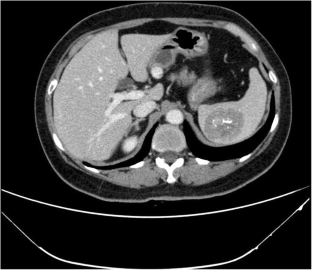

Fig. 1